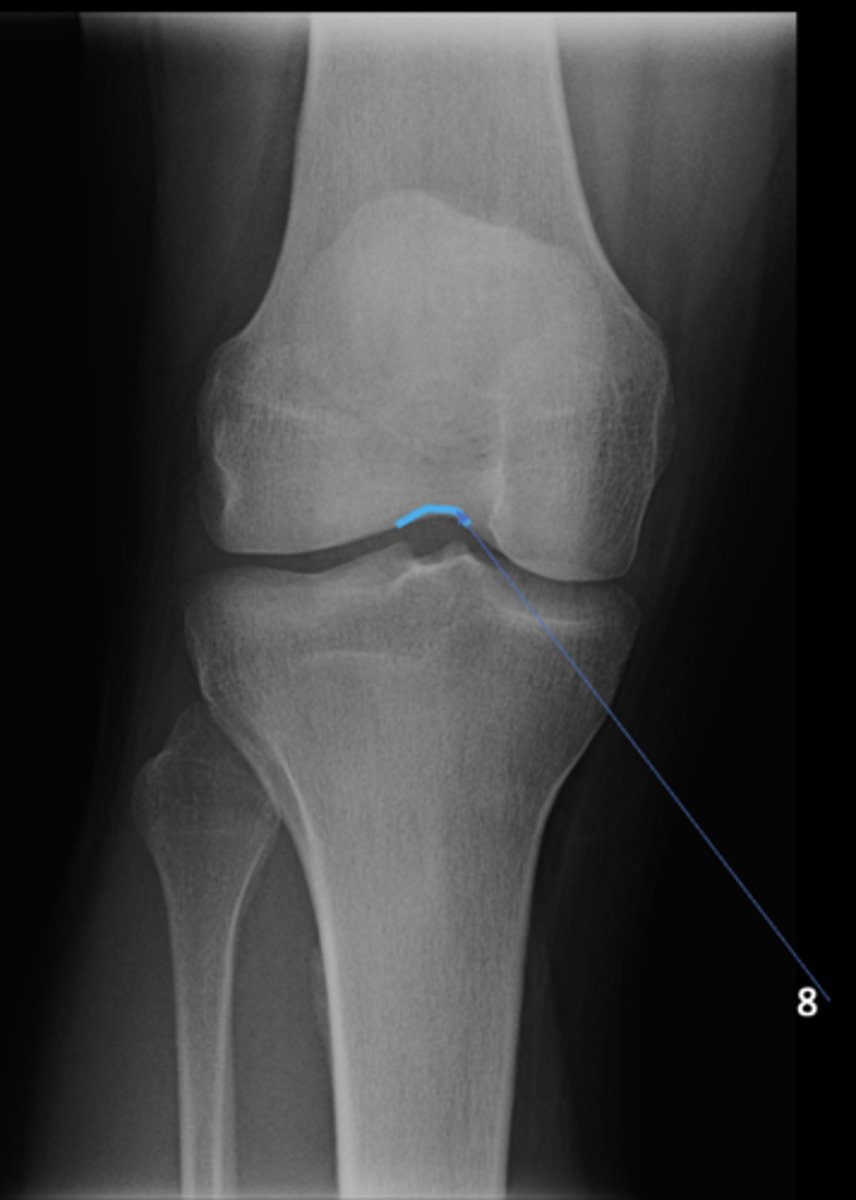

8

New cards

Left ischial spine

ID 8

<p>ID 8</p>

9

Right fovea capitis

ID 9